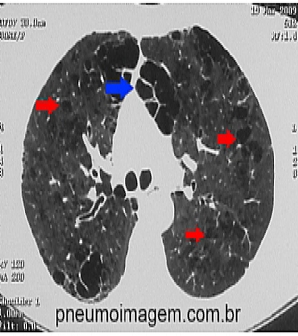

Veja imagens de DPOC no PneumoImagem, clique aqui.